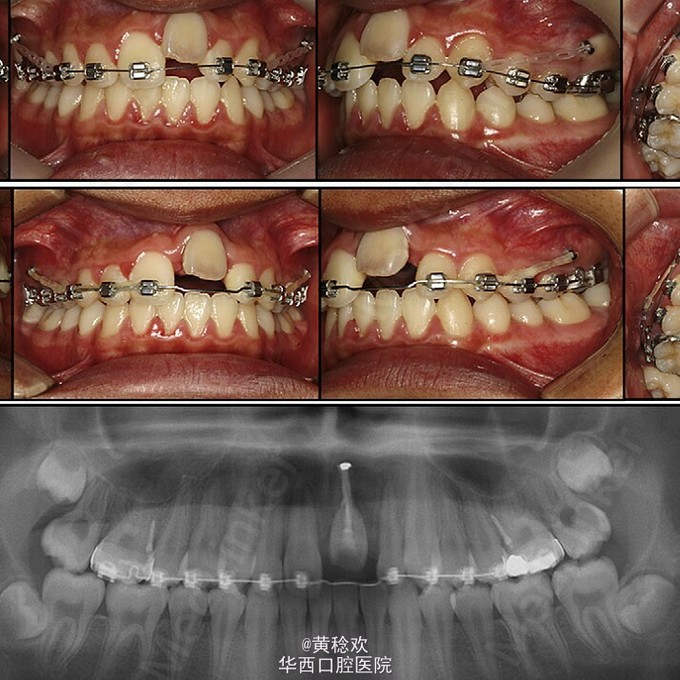

牙齿脱位对牙周膜、牙槽骨、牙龈、牙髓和牙骨质造成严重损害。脱位牙再植后经常伴有牙骨粘连等并发症。牙骨粘连指的是局部牙骨质和周围牙槽骨融合,多起因为牙齿正在萌出过程中或萌出后受到机械性、温度或者代谢产物刺激,对牙周膜造成损伤,好发于恒切牙。 牙骨粘连可通过临床和放射片检查诊断。临床检查包括低咬合状态、叩诊和松动度测试,最明显的特征是即便该牙施加正畸牵引力后也无法移动。整个牙的牙骨粘连可以通过放射片显示,其特征为无明显的牙周膜影响。但是如果该牙只有颊侧或者舌侧粘连,放射片上很难判断。近年来,CBCT的引入,可以逐渐将放射检查视野拓宽到3D层面,增强了对骨牙粘连的准确性。治疗骨牙粘连的方案包括:拔除、截冠、修复、手术半脱位、骨切开术和牵张成骨术等。